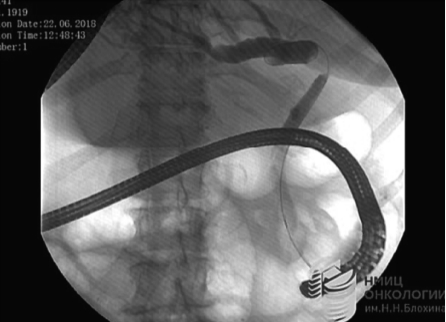

Пациентке выполнена дуоденоскопия, папиллосфинктеротомия, ЭРХПГ, холангиоскопия, билиодуоденальное стентирование левого долевого протока пластиковым стентом.

При РГ-исследовании: внепеченочные желчные протоки не расширены на всем протяжении. На уровне отхождения левого долевого протока (в анамнезе правосторонняя гемигепатэктомия) определяются деформация просвета и сужение протока протяженностью до 1,5 см, стенка неровная. При этом левый долевой проток извитой, образует острый угол с общим печеночным протоком. Протоки левой доли печени выраженно расширены, долевой до 2 см, сегментарные до 1 см.

При визуальной оценке в верхней трети общего печеночного протока, на границе с долевым протоком определяется внутрипросветное экзофитное полуциркулярное образование до 15 мм, перекрывающее просвет протока более чем на 2/3. Ткани мелкобугристые, гиперемированные. Под визуальным контролем выполнена множественная биопсия тканей (цитология + гистология). Далее под РГ-контролем также выполнена биопсия из зоны стриктуры, под визуальным контролем струна-проводник заведена в левый долевой проток за зону сужения. По струне-проводнику установлен пластиковый билиодуоденальный стент (Olympus 15 см, 8.5 Fr). По стенту отмечено поступление желчи (рис. 5).

Рис. 5а. Изображение ретроградной холангиографии.

Fig. 5a. ERCP image.

Рис. 5б. Изображение транспапиллярной холангиоскопии с помощью системы SpyGlass

Fig. 5b. SpyGlass image.